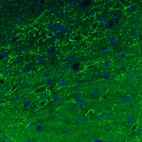

Immunohistochemical staining of rat globus pallidus shows strong immunoreactivity in GABAergic neural fibers.